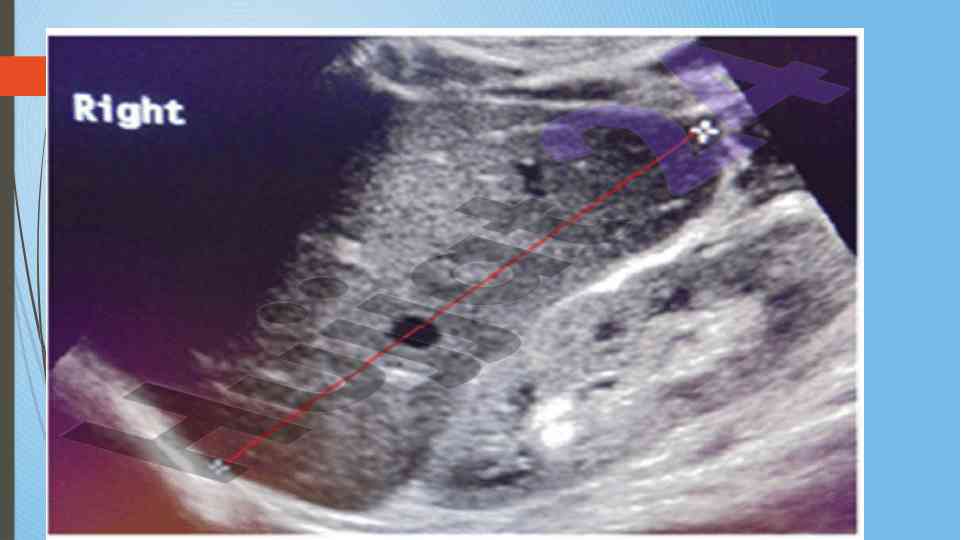

Диссертатсия давомида сурункали гепатитларнинг ультратовуш ташхиси ва этилогиясини ўрганиш. Аутоиммун ва ноалкоголь гепатитларнинг хусусиятлари таҳлил қилинган.